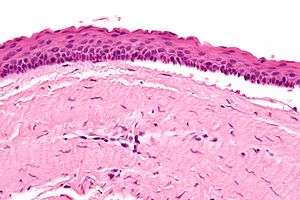

| Micrograph of a keratocystic odontogenic tumour. H&E stain. | |

The definitive diagnosis is by histologic analysis, i.e. excision and examination under the microscope.

Under the microscope, KCOTs vaguely resemble keratinized squamous epithelium;[3] however, they lack rete ridges and often have an artifactual separation from their basement membrane.